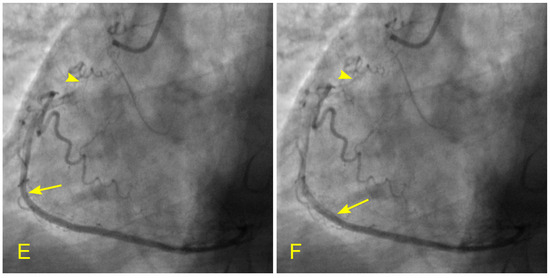

Figure 17.

(A,B) Antegrade flow in the right coronary artery (RCA). These images are in continuous sequence. (A) The artery is completely full of contrast in black. There is a severe 80% lesion in the mid-segment of the RCA (arrowhead). (B) In the ostium of the RCA, the blood, in white, moves in at the beginning of diastole (arrow). (C–F) Antegrade and retrograde flows in the right coronary artery (RCA). (C) Now, the blood, in white, continues to move in at the proximal segment of the RCA (arrow). (D) The blood, in white, reaches the center of the mid-segment where the lesion is located (arrowhead). The contrast looks darker. This is the interface location between the antegrade and retrograde flow at the transition from diastole to systole. (E) The blood, in white, reaches the beginning of the distal part of the mid-segment (arrow). At this location of the transition between systole and diastole, the contrast still looks dark (arrowhead). (F) The contrast looks darker in the mid-segment, and in the proximal segment, the contrast in black looks darker and is at a standstill (red arrow). (G,H) Antegrade and retrograde flow in the right coronary artery (RCA). (G) The blood, in white, reaches the beginning of the distal segment (arrow). At the location of the transition between systole and diastole, the contrast still looks dark (arrowhead). The contrast looks darker in the proximal segment, where the contrast in black is at a standstill (red arrow). (H) The blood, in white, reaches the middle of the distal segment (arrow). At the location of the transition between systole and diastole, the contrast still looks less dark (arrowhead). The contrast looks lighter in the proximal segment (red arrow).